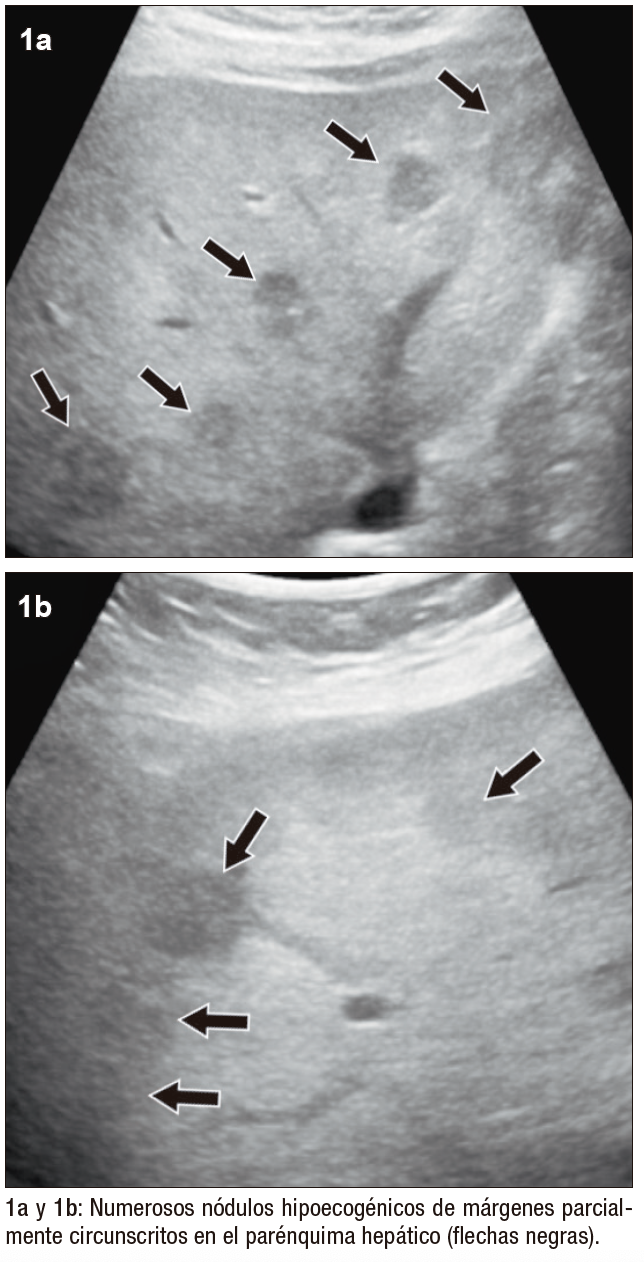

Posteriormente, se realiza una ecografía abdominal en la que se muestran innumerables nódulos hipoecogénicos, de márgenes parcialmente circunscritos, con calcificaciones en su interior, algunos causantes de retracción capsular, sin evidencia de flujo vascular con Doppler color (Figura 1). Tras estos hallazgos, se continúa la valoración mediante TCMD (Tomografía Computada Multi detector) con contraste endovenoso, donde se observan, en consonancia con la ecografía, numerosos nódulos isodensos e hipodensos, con realce en anillo en fases arterial y venosa, distribuidos en ambos lóbulos hepáticos.

Figura 1. Ecografía hepática con transductor convexo, en modo B (a y b) y Doppler color (c)